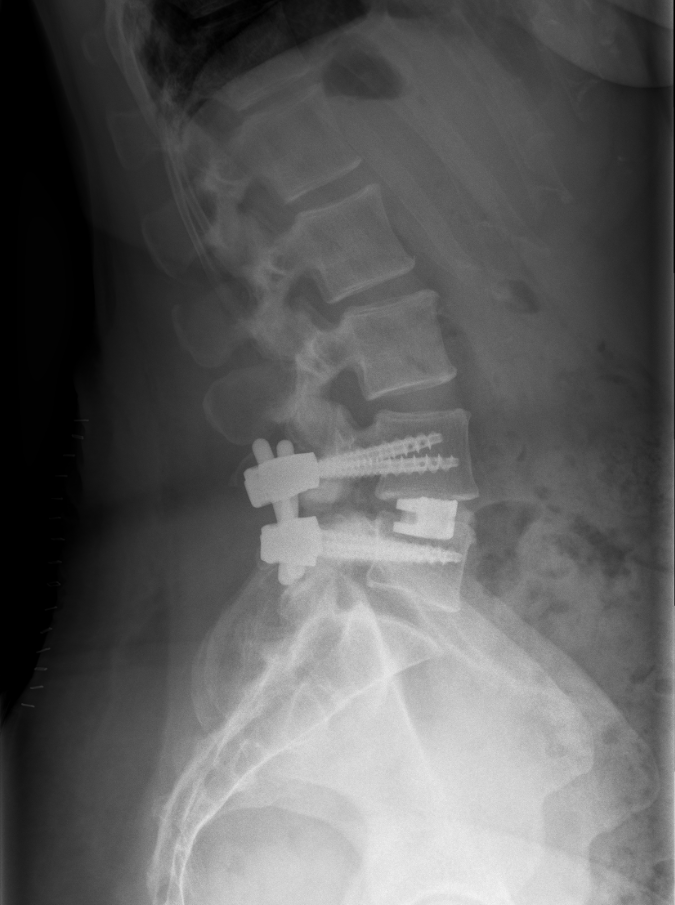

TLIF LWK4/5

Laterales Röntgenbild eines Patienten wenige Tage nach Durchführung eines TLIF LWK4/5.